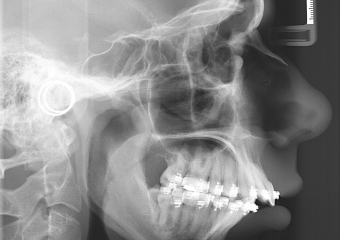

Telerradiografia perfil após cirurgia realizada em 2015 - Clínica Cliniface

Telerradiografia perfil após cirurgia realizada em 2015